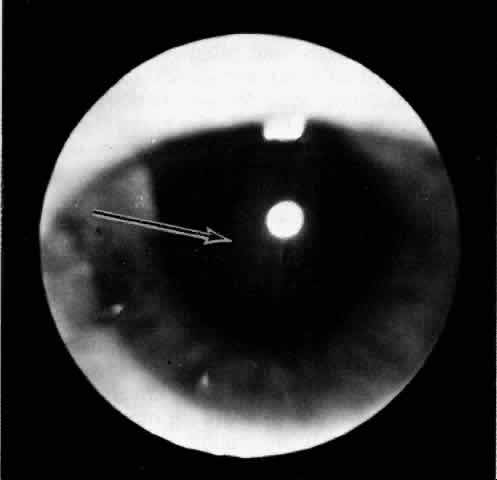

| A ciliochoroidal effusion may be mistaken for a malignant melanoma in the

ciliary body or choroid.26 Transillumination, fluorescein angiography, ultrasonography, and computed

tomography may assist in distinguishing an effusion from a melanoma. Increased

transillumination may be observed with a serous ciliochoroidal

effusion and has been referred to as Hagen's sign.27 Pigmented choroidal melanomas may not transilluminate; however, in some

cases of ciliary body melanoma, particularly nonpigmented tumors, transillumination

may not be defective. In fact, in some cases the tumor

may even transilluminate. A rare case of coexisting ciliochoroidal detachment